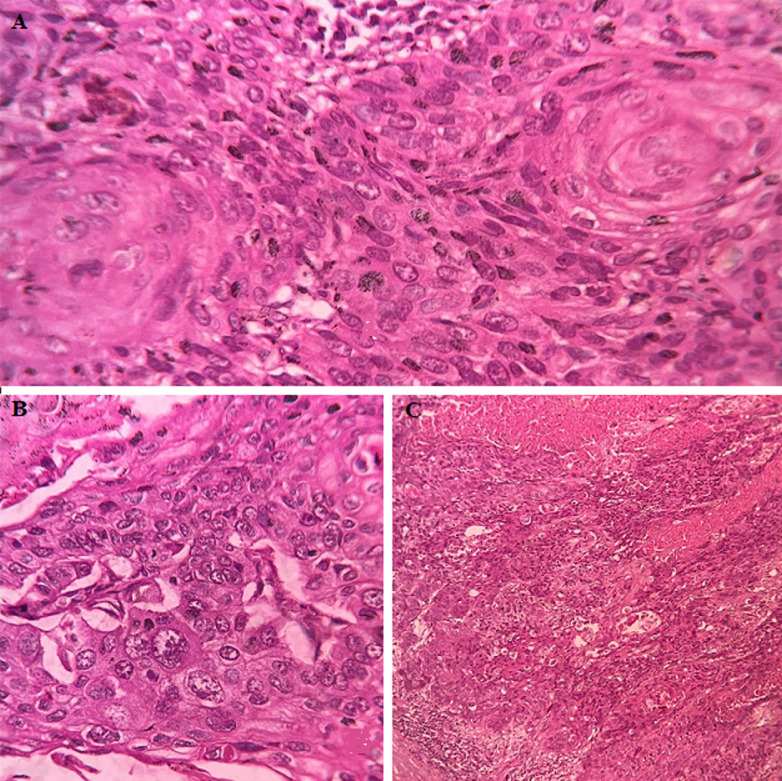

In renal squamous cell carcinoma tissue, irregular nest and malignant cells are arranged in sheet.Fig 1. Histological section of renal squamous cell carcinoma.1

1. Datta, Pragyamita. "Squamous cell carcinoma in kidney with chronic pyelonephritis and pyelonephrosis: a rare case."The Pan African medical journal 45.31 (2023): 31.39117. Distributed under Open Access license CC BY 4.0, the original image's title was changed to "Histological section of renal squamous cell carcinoma".